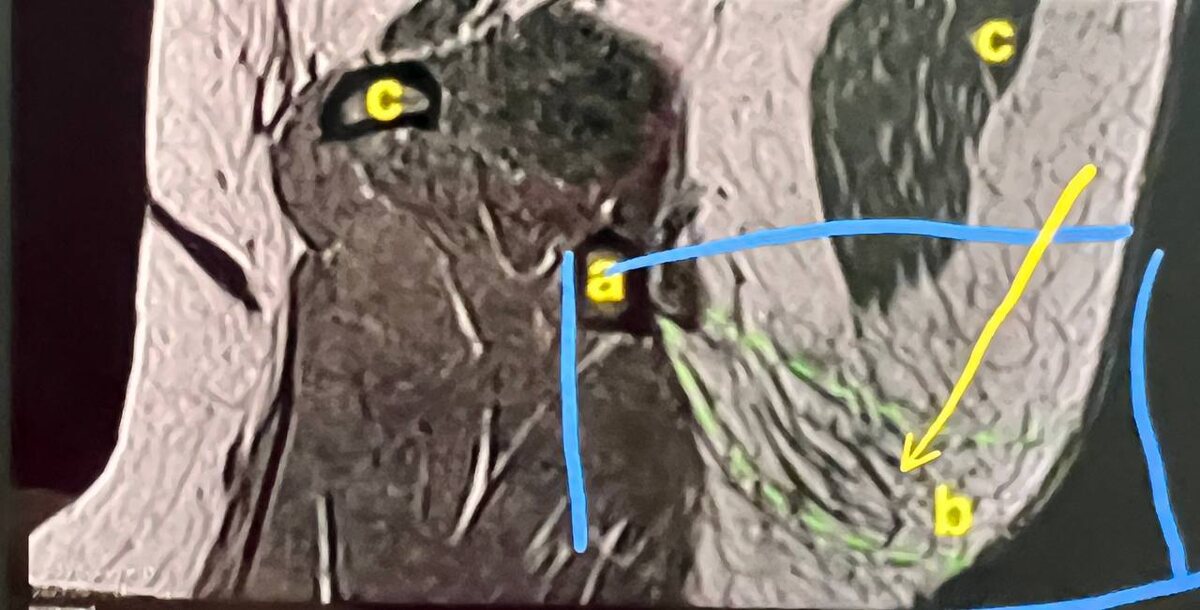

Подъягодичная складка -

это соединительнотканная структура, которая крепится к кожи и костям.

Она формируется благодаря специальной связке и играет ключевую роль в эстетике ягодиц.